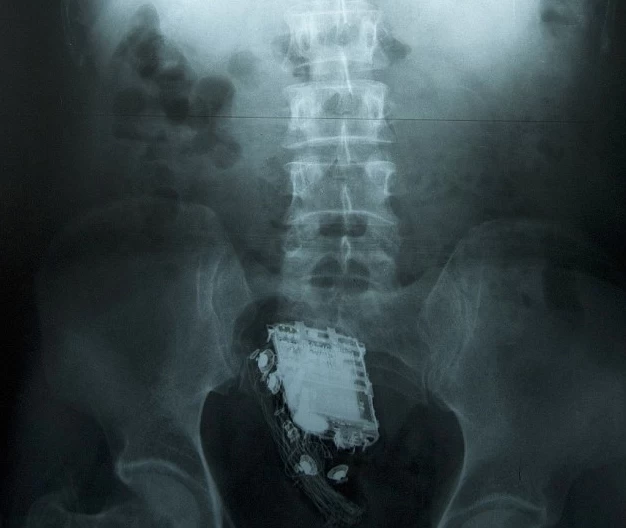

如果懷疑有人藏匿毒品,機場會對疑似藏匿毒品者進行更深入的X光檢查,這種檢查比一般乘客的檢查耗時更長。如果發現毒品包,藏匿者就必須等待排便,聽起來可不太舒服。在紐約甘迺迪機場,這種排便是在「毒品廁所」進行的,這種廁所會在使用後自動清洗藏匿的毒品包。

這些毒品包裝通常由毒品(通常是可卡因、海洛因或冰毒)壓縮至盡可能緻密的狀態,然後裝入某種乳膠容器中。這種乳膠容器可能是保險套或氣球,沒錯,但這還不是全部。接下來,氣球會被塗上一層密封劑,通常是蠟或某種工業密封劑。包裝內可能還會包含鋁箔或其他物品,以乾擾任何可能檢測到毒品的機器。這些包裝形狀統一,兩端呈錐形,看起來像是機器加工的——這並非某人用手捏氣球,而是一項精心策劃的專業行動。

至於容量,嗯,其實沒人知道。通常情況下,一個搬運工或搬運騾子會攜帶大約50到100個這樣的包裹,但也有人被發現攜帶超過200個——重達五磅——藏在消化道裡。有時,搬運工會服用一些止瀉藥來抑制身體排出包裹的衝動,並且選擇在飛行途中不進食。正如瑪麗·羅奇在她精彩的新書《吞嚥:消化道奇遇記》中所述,一些長途國際航班的乘務員會記錄任何拒絕進食的乘客,以便在飛機著陸後交給安保人員。因此,搬運工會感到極度不適、疑神疑鬼,犯下各種違法行為,最重要的是,他們可能還很餓。